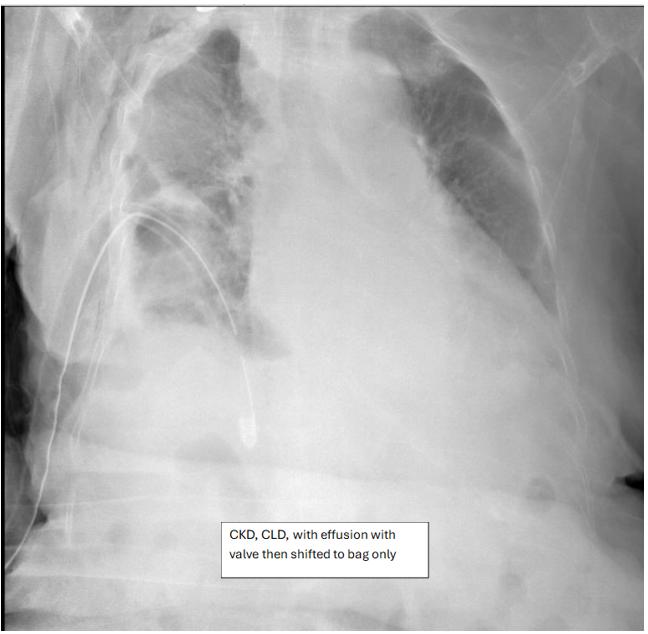

• Patients having multiple co-morbidities (e.g., chronic liver disease, chronic kidney disease and heart failure) who were not surgical candidate were discharged on bag and follow-up shows improvement.

Figure 6